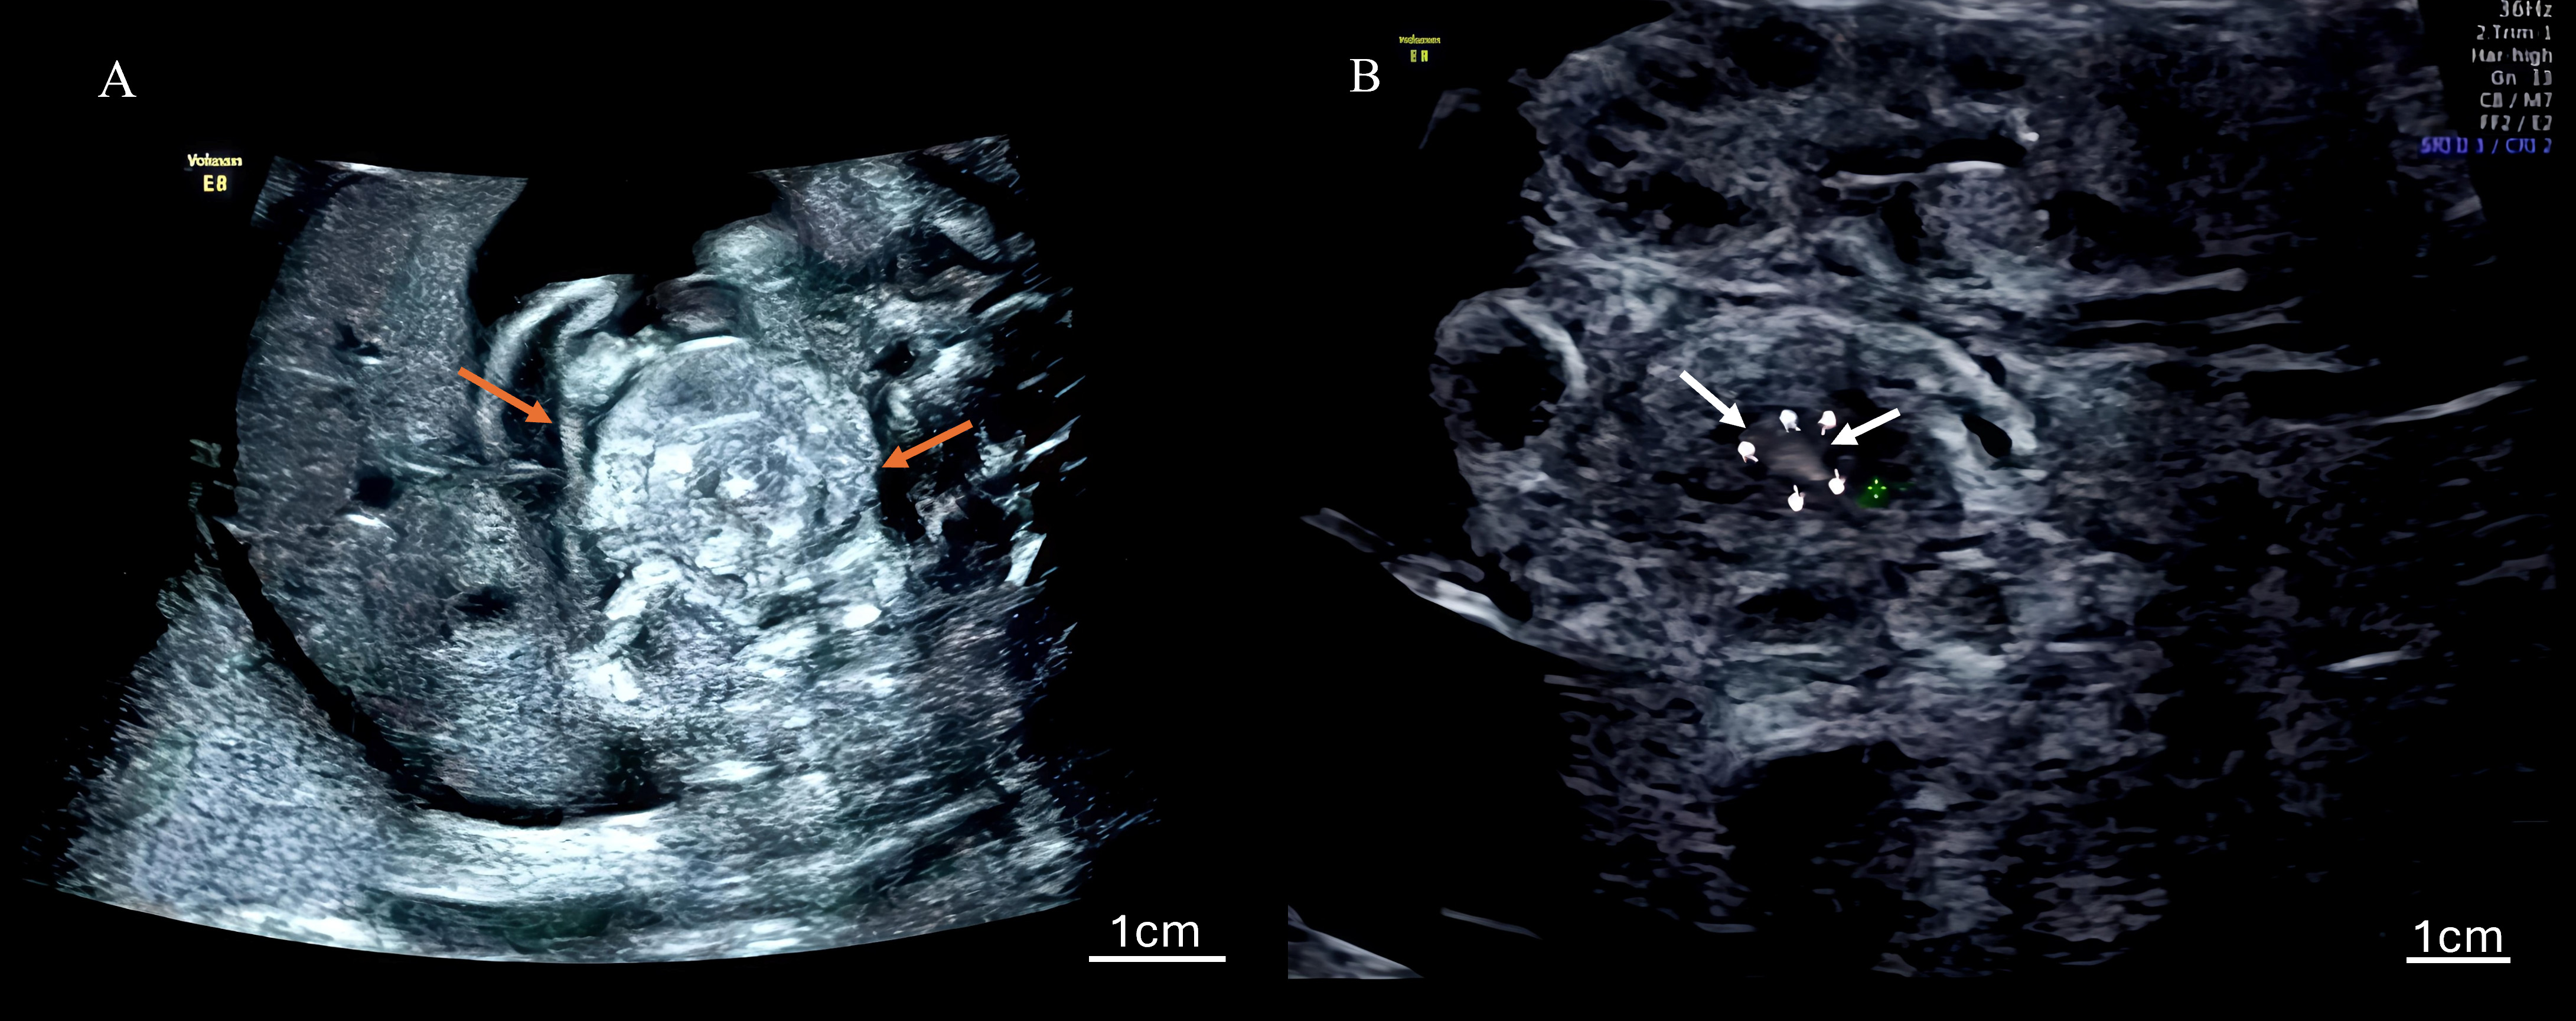

The ultrasonographic findings for all seven cases are summarized in Table 1, which details the gestational age at diagnosis and the presence of key signs. Table 2 quantifies the frequency of findings across all 27 examinations. Characteristic signs included the whirlpool sign (Fig. 1), annotated with arrows to highlight the spiral-shaped mass of dilated bowel loops), a spiral-shaped mass of dilated bowel loops, and the vascular spiral sign (Fig. 2A: 2D ultrasound; Fig. 2B: 3D ultrasound, with arrows indicating the mesenteric vein swirling around the mesenteric artery), observed in all cases (7/7). Nonspecific findings included bowel dilation (7/7), ascites (6/7), abdominal pseudocysts (2/7), coffee bean sign (2/7), hydramnios (1/7), and increased middle cerebral artery flow velocity (1/7). Among the 27 examinations, the detection rates were as follows: whirlpool sign, 20/27 (74.1%); vascular spiral sign, 20/27 (74.1%); bowel dilation, 23/27 (85.2%); ascites, 18/27 (66.7%); cystic abdominal masses, 5/27 (18.5%); coffee bean sign, 2/27 (7.4%); hydramnios, 3/27 (11.1%). Detailed case descriptions are provided below:

Fig. 1. Two-dimensional ultrasound image of the whirlpool sign. (A, B) Images characterized by a spiral-shaped mass of dilated bowel loops, observed in all seven cases of fetal intestinal volvulus, confirming the diagnostic reliability of this technique. Arrows indicate the spiral configuration of the dilated bowel loops, and a scale bar is included for spatial reference. The little finger indicates the center of the whirlpool sign.